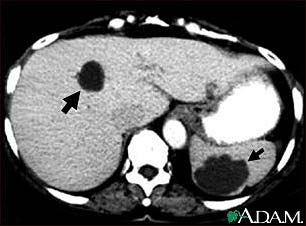

CAT scanners (also called Computed Tomography, or CT, scanners) were the first tomographic scanners developed for medical applications. They use an array of x-rays beams projected from many angles around the body to create anatomical images like the one below.

(a)View of a clinical X-ray tomography instrument.

(b)Cysts in the liver and spleen appear in a CAT scan image.

Figure 7:Image from http://